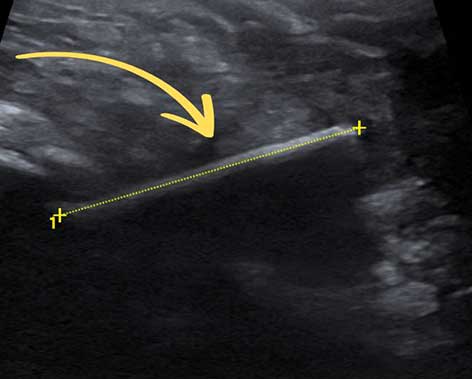

Im Ultraschall zeigte sich der Auslöser dann sofort: ein deutlich sichtbarer, länglicher Fremdkörper. „Ich sagte den Besitzern, dass es für mich wie ein Holzspieß aussieht“, erinnert sich die Oberärztin: „Da fiel ihnen ein, dass Sparky im Mai beim Grillen möglicherweise einen Schaschlikspieß erwischt hatte. Damals konnten sie aber nicht nachvollziehen, ob er ihn überhaupt erwischt, gefressen oder nur angekaut hatte.“

Ultraschall zeigt länglichen Fremdkörper im Magen.